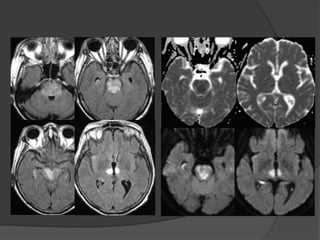

Case 2: 41M, AMS, s/p

seizure

Courtesy: Matt Fox, MD

Feb 2014June 2014

DWI FLAIR

T2 T1

T2 ADC

ADC

DWI

Patchy restriction of diffusion in a

cortical distribution (but not in all

areas of edema)

Case 2 Diagnosis: MELAS

 MELAS (mitochondrial encephalopathy with lactic

acidosis and stroke-like episodes

 Characterized by 'stroke-like' episodes, typically in

childhood or early adulthood (90% present before 40

years of age)

 Encephalopathy, seizures, dementia, lactic acidosis ,

muscle weakness

 CT: Atrophy, multiple infarcts involving multiple vascular

territories. Parieto-occipital and parieto-temporal

involvement is most common, basal ganglial calcification

• MRI: Swollen gyri with increased T2 signal, increased

signal on DWI (T2 shine through) with no change on ADC

indicating vasogenic edema

• MR spectroscopy: Elevated lactate